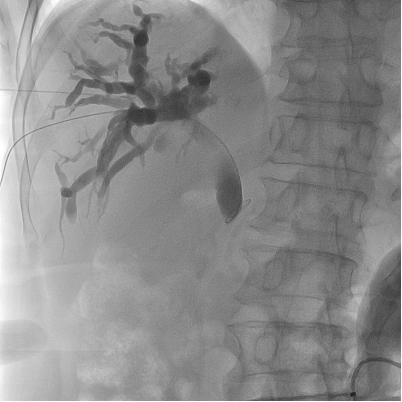

DSA引导下胆道穿刺引流

包括各类胸腹腔积液、心包积液、腹腔盆腔脓肿的穿刺抽吸置管引流。以及梗阻性黄疸时可行超声或者DSA引导下经皮经肝胆管、胆囊穿刺置管,减黄效果立竿见影,又为进一步治疗建立了“救命”通道。